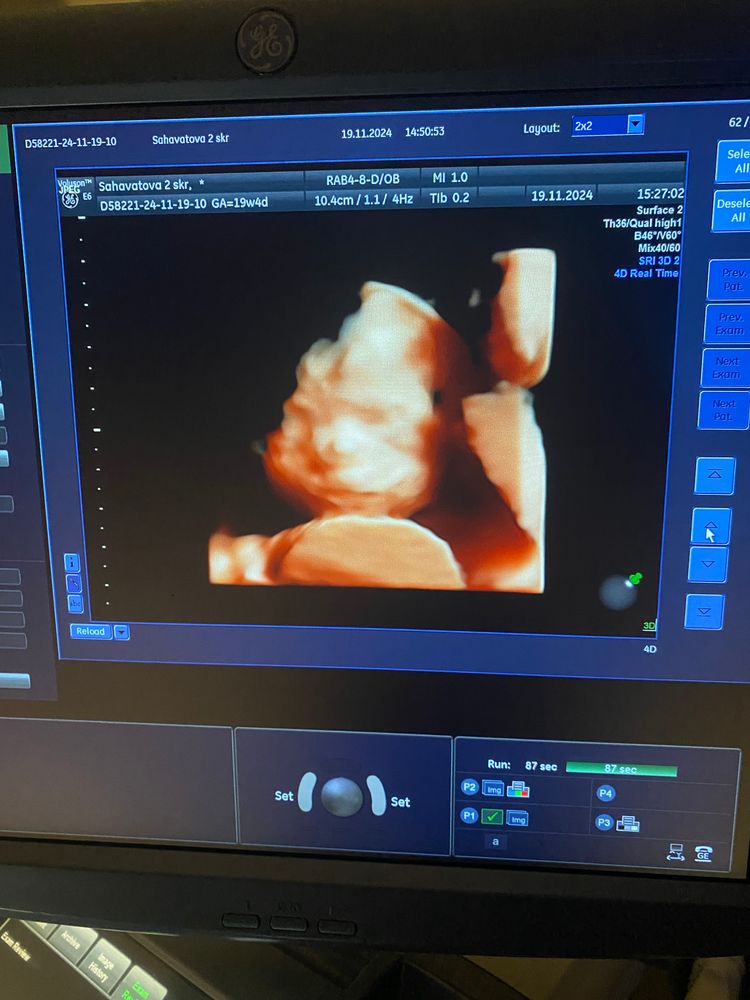

2 скрининг🩷☺️🤰🏼

УЗИ, КТГ, доплерВчера сходила на второй скрининг на сроке 19 недель и 4 дня🩷☺️

Вот такую мы ждём принцессу🥺🥺🥺

Крошка все время сосала свой пальчик и пыталась закрыть личико рукой.